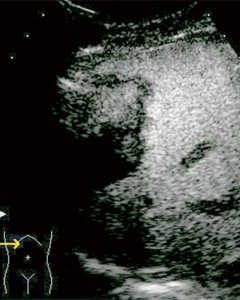

■ Real-time Virtual Sonography(RVS)と超音波造影(図4,5)

CT・MRI・超音波のボリュームデータから,探触子と同一方向のMPR像をリアルタイムに描出する機能である。これにより,造影CTと造影超音波像,造影超音波前後の画像を任意の方向から比較観察が可能となり,治療効果判定等に有効である。

図4 HCCのRFA後のPVS (画像ご提供:島根大学 佐藤秀一先生)

a:焼灼後のCT像

b:contrast像